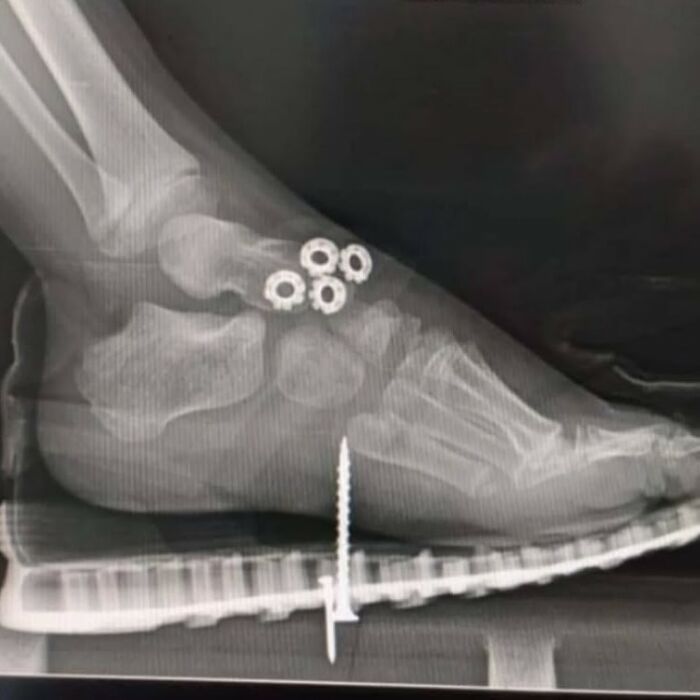

Piercing de Aquiles